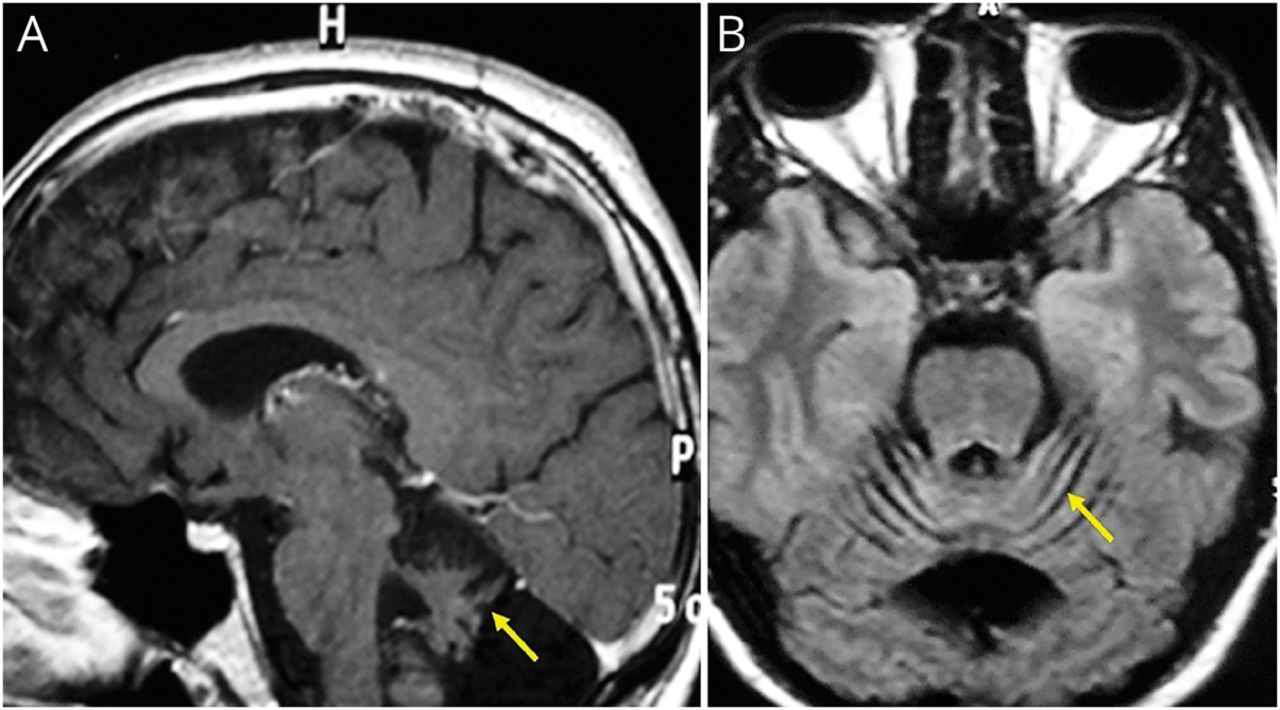

34岁的西班牙人与艾滋病毒感染没有治疗(CD4 20 /μL,病毒载量1.9/106拷贝/毫升)提出了4个月的眩晕、共济失调、扫描演讲符合pancerebellar综合症。核磁共振扫描(图)表明小脑萎缩。脑脊液显示正常细胞计数、蛋白质和葡萄糖水平,不反应的性病研究实验室测试。脑脊液PCR负了巨细胞病毒、水痘带状疱疹1型和2,巴尔,约翰·坎宁安和疱疹病毒6,但阳性(JC)病毒。JC病毒颗粒细胞neuronopathy (GCN)被诊断。JC病毒变异可能很少感染小脑颗粒神经元而不是少突胶质细胞在典型的渐进多焦点的脑白质病与白色物质参与。1,2鸡尾酒疗法(齐多夫定、拉米夫定、依法韦伦)立即开始,在12个月里,轻微的症状改善MRI扫描持平。临床医生应该怀疑JC病毒株感染生产GCN艾滋病患者小脑萎缩症状2和开始HAART promptly-immune调整炎症综合征通常不是一个问题在孤立的情况下JC病毒之下。